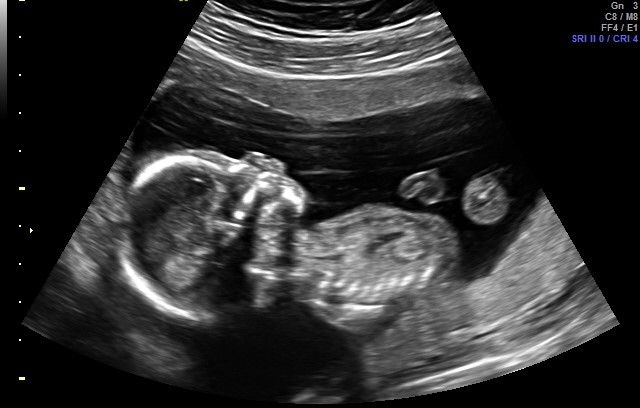

I was told a boy by this ultrasound photo, but i am having a hard time understanding the picture. Can someone help? I was sure I was having a girl, too, and this isn’t helping my confusion! https://uploads.tapatalk-cdn.com/201...d73731cca5.jpg